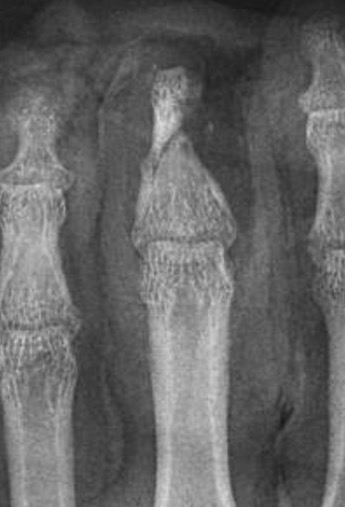

Thumb replant

![]()

Background

Thumb has first priority

A successfully replanted thumb is always better than any reconstruction

- thumb provides 40% of hand function

Level

Detipped thumb can be successful

- need dorsal veins in stump

- need 4mm of skin proximal to nail plate

- all efforts should be made to preserve thumb length